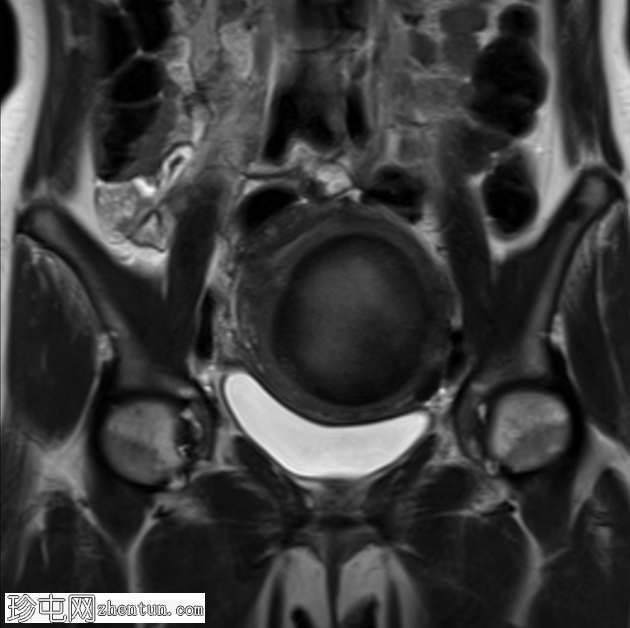

轴位

T2加权像

子宫前壁可见一边界清晰的壁内病灶,大小约7.8 × 7 × 6.8 cm。脂肪抑制T1加权像呈弥漫性高信号,T2加权像呈高信号伴低信号环,无扩散受限及对比增强。

此外,可见一个2厘米的带蒂浆膜下肌瘤,以及较小的肌壁内和浆膜下肌瘤;所有肌瘤均呈均匀强化。

盆腔内可见少量游离液体,可能为生理性。